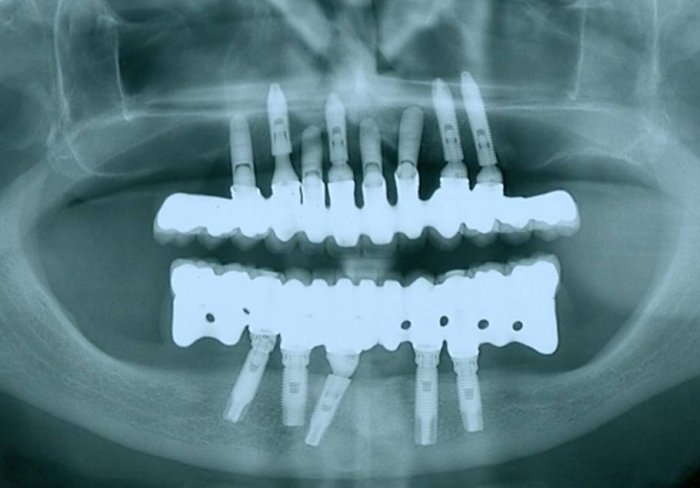

Imagens iniciais, dos dentes e implante comprometidos realizados por outro profissional